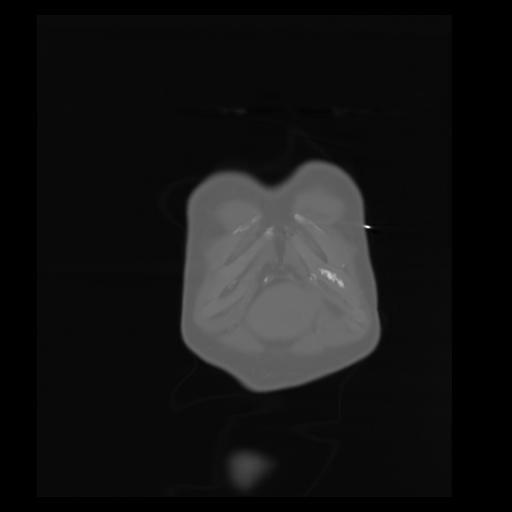

29 CUERPO,CE,Coronal,3.000,CUERPO,Coronal,